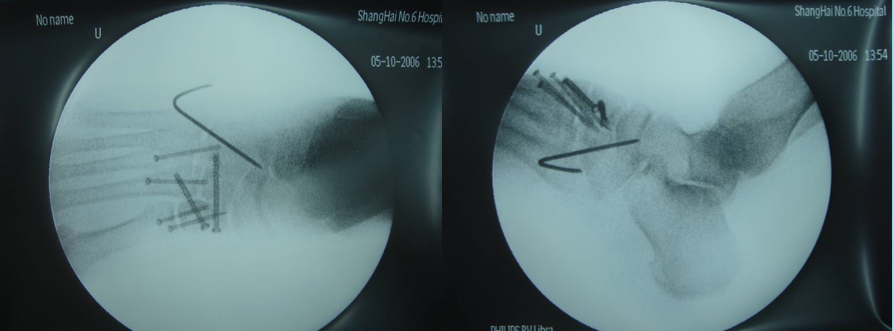

Lisfranc损伤骨折复位标准:1、C形臂透视显示正、侧、斜位均为正常解剖复位2、如复位后第1、2跖骨基底间隙和内、中楔骨间隙<2mm,跖跗骨轴线<15°为近解剖复位,可以接受,超过这个范围的移位则无法接受3、复位好后,沿第一跖骨轴线向内侧楔骨逆行拧入一枚4.0mm皮质骨螺钉。螺钉由关节远侧1.5-2.0cm处进入,平行于足底或略向跖侧。

4、从内侧楔骨向第二跖骨置入一枚螺钉,重建韧带。螺钉自内侧楔骨近端的背侧置入,指向第二跖骨背侧皮质的下方,螺钉应通过4层皮质,确保对第二跖骨的双皮质固定

术后管理石膏固定4~6周;如果固定稳定,术后两周可开始功能锻炼,4~6周部分负重,六周后完全负重;术后6~8周可拔去克氏针,术后3~4月可取出螺钉。有些人主张若无症状出现,可无限期地留置螺钉于体内